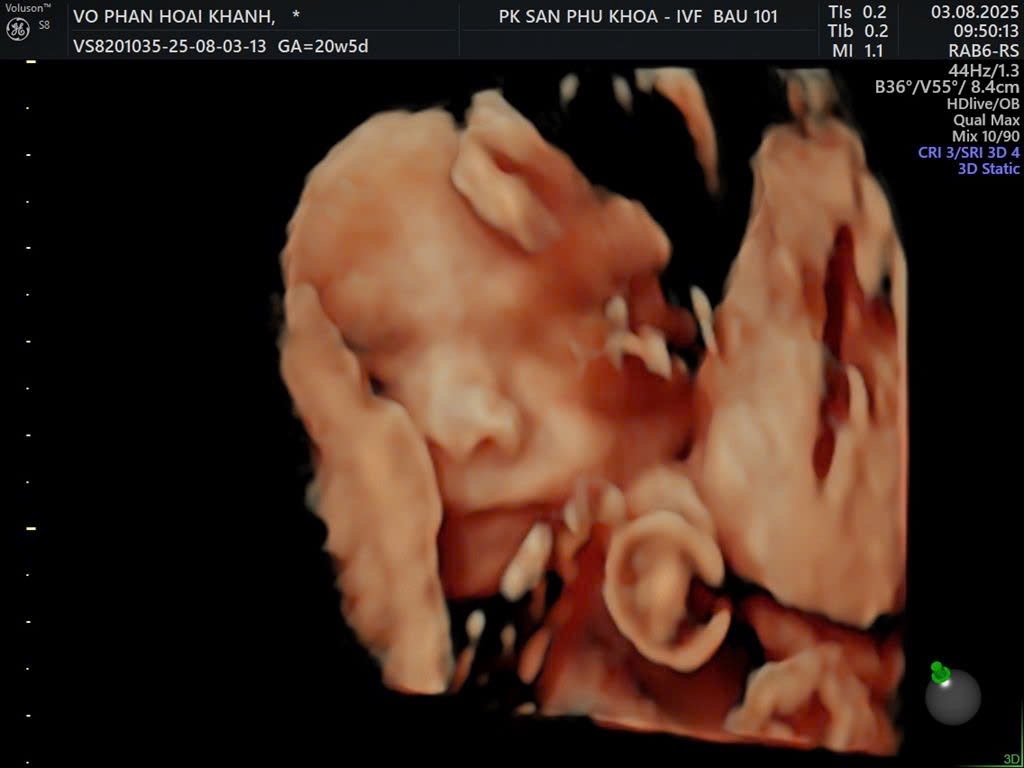

Võ Phan Hoài Khánh